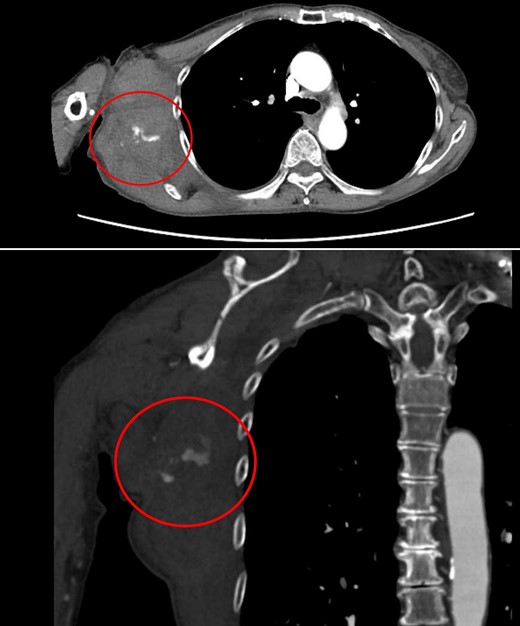

Four days later, the patient was hospitalized for rapidly worsening swelling and pain, and was readmitted with a diagnosis of rebleeding from the chest wall. Physical examination revealed a fist-sized subcutaneous mass on the right side of the chest, with severe pain. Laboratory data indicated anemia (Hb 7.8 g/dl) and no coagulation disorder: % prothrombin time (PT) 115.1%, prothrombin time-international normalized ratio (PT-INR) 0.93, and activated partial thromboplastin time 23.6 s. Computed tomography (CT) at the time of the first hemorrhage showed the hematoma on the right chest and anterior to the scapula (Fig. 2). Contrast-enhanced CT at the time of rebleeding showed an increase in hematoma and extravasation in the peripheral right lateral thoracic artery (Fig. 3). The patient was immediately treated with emergency angiography, which revealed active bleeding from a pseudoaneurysm of the right lateral thoracic artery. Thus, coil embolization was performed (Fig. 4). There were no TAE-related complications and the patient was discharged to home on the fifth hospital day. Oral clopidogrel was resumed and there has been no recurrence of bleeding.

Chest CT at the time of the first bleeding showed formation of a hematoma on the right chest and front of the scapula.

Contrast-enhanced CT at the time of the second bleeding showed growth of the hematoma and extravasation of contrast agent in a branch of the right lateral thoracic artery.